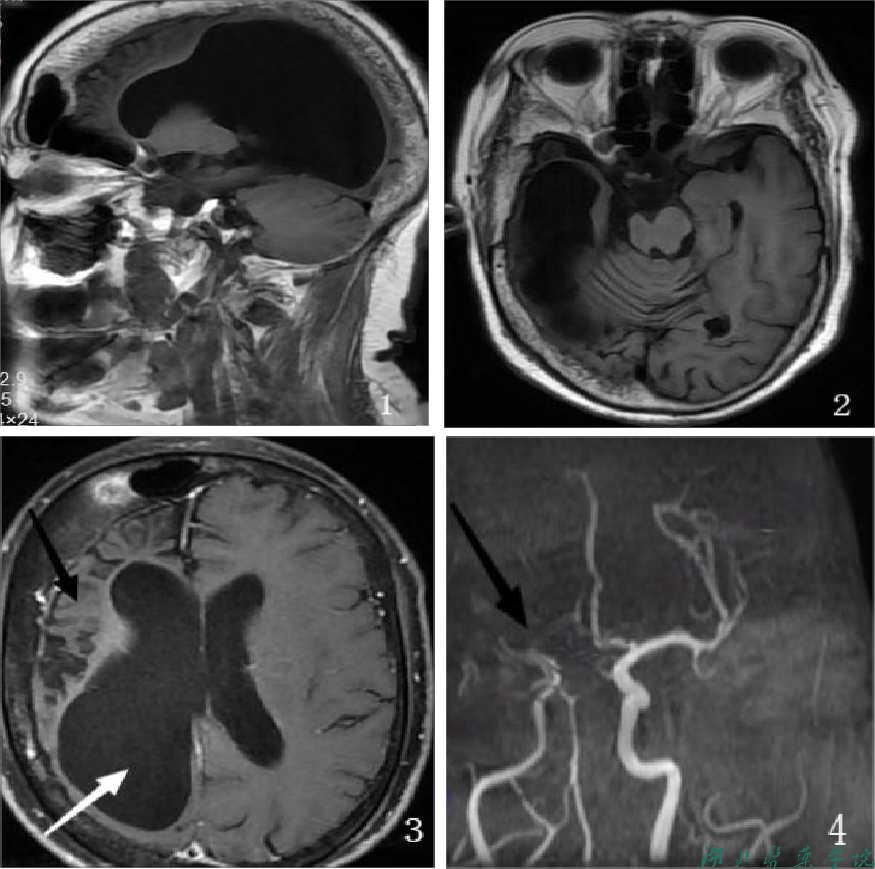

| 磁共振平扫+增强 | 右侧大脑半球皮层及皮层下脑实质体积缩小,右侧残余脑白质T2t1a1信号增高,右侧大脑半球脑沟、裂增宽,右侧脑室明显较对侧扩大,中线结构稍向右侧偏移。右侧额颞顶枕骨板障明显增厚。右侧额窦较对侧明显扩大,其内气化良好。左侧放射冠区见多发斑点状异常信号,T2WI及T2f1a1r是高信号,左枕叶(侧脑室后角下)见一囊状T2WI高信号影,直径约0.9cm。颅内未见明显流空信号团注G-DTPA增强扫描:颅内未见明显导常强化灶。 | 1.戴克-戴维多夫-马森(Dyke-Davidoff-Masson)综合征可能性大。 2.左侧放射冠区多发腔梗。 3.左侧枕叶囊肿。 |

| 磁共振血管成像 | 右侧大脑中动脉M1段纤细,远端分支未见显影;左侧大脑后动脉P2段及右侧大脑前动脉A2、A3段中重度狭窄;颅内未见明显异常血管显示。 | 1.右侧大脑中动脉M1段纤细、重度狭窄、闭塞;左侧大脑后动脉P2段及右侧大脑前动脉A2、A3段中重度狭窄。 2.双侧胚胎型大脑后动脉。 |

1. Dyke-Davidoff-Masson综合征( Dyke-Davidof-Masson syndrome,DDMS)是一种罕见的中枢神经系统疾病,是脑偏侧萎缩的常见病因临床以反复癫发作、面部不对称、一侧肢体偏瘫、智力发育低下及精神异常等为特征。典型影像学表现为单侧大脑半球萎缩、同侧侧脑室扩张、部分脑实质有较大的软化灶、同侧颅骨增生、鼻窦及乳突窦增大等。由Dyke、Davidoff和Masson于1933年首先报道。

2. 临床进程是不对称的大脑半球增长发育,伴有一侧萎缩负占位效应。脑实质容量的减低导致了同侧侧脑室和脑沟扩大。这种适应性改变,其结果导致同侧颅盖骨增厚、以及鼻旁窦增大。

3. 大脑镰移位是DDMS的一种关键性改变

典型影像学表现为:单侧大脑半球萎缩、同侧侧脑室扩张、部分脑实质有较大的软化灶同侧颅骨增生、鼻窦及乳突窦增大等。